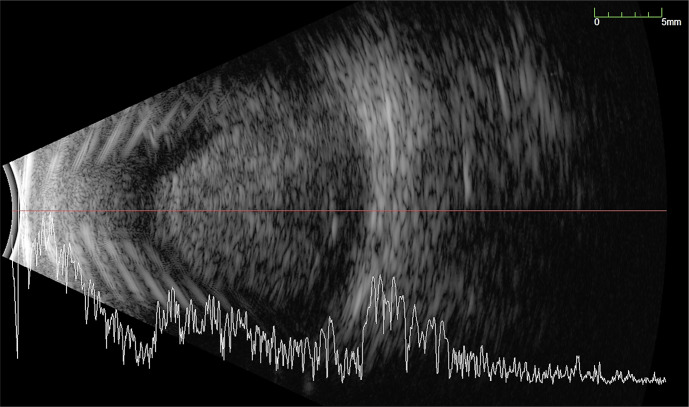

大量脉络膜上出血(SCH)是一种毁灭性的并发症,具有显著的发病率和不良的视觉和解剖结果。常规的处理方法是在手术引流前观察7-14天。然而,视网膜的永久性结构变化可能在这段时间内发生。脉络膜上注射重组组织型纤溶酶原激活剂(TPA)可加速血块分解,有助于早期手术引流。我们报告了一个病例系列,涉及黄斑块状SCH (MSCH)的早期引流辅助重组组织纤溶酶原激活剂(r-tPA)。病例介绍:回顾性分析3例累及黄斑的mscs患者,在出血后24小时内行脉络膜上r-tPA治疗,在注射r-tPA后48小时内早期引流,并联合玻璃体切除和填塞。所有患者均在初始损伤后24 h注射100µg重组TPA。注射r-tPA后6-48 h进行SCH引流。所有患者早期引流成功,视力均有改善。1例SCH复发,但再次成功治疗。结论:r- tpa辅助SCH早期引流技术是安全的,在恢复黄斑累及的mscs患者的视觉功能方面具有广阔的应用前景。我们的小样本表明,在出血24小时内注射100 μg/0.4 mL的r-tPA,可以在初次损伤后第2天手术引流SCH。需要更大规模的研究来进一步调查哪些患者可能从这种治疗中受益。

Introduction: A massive suprachoroidal haemorrhage (SCH) is a devastating complication with significant morbidity and poor visual and anatomic outcome. Conventional management is to observe for 7-14 days before surgical drainage. However, permanent structural changes in the retina can occur within this timeframe. Suprachoroidal injection of recombinant tissue plasminogen activator (TPA) may speed up clot breakdown and aid early surgical drainage. We present a case series of macula-involving massive SCH (MSCH) treated with early drainage aided by recombinant tissue plasminogen activator (r-tPA).

Case presentation: Retrospective case series of 3 patients with macula-involving MSCH treated with suprachoroidal r-tPA within 24 h of bleed and early drainage of SCH within 48 h of r-tPA injection, combined with vitrectomy and tamponade. 100 µg of recombinant TPA was injected into the SCH 24 h following initial injury in all patients. Drainage of the SCH was then performed 6-48 h after the injection of r-tPA. Early drainage was successful and visual improvement was seen in all patients. One patient had a recurrence of SCH but was successfully re-treated.